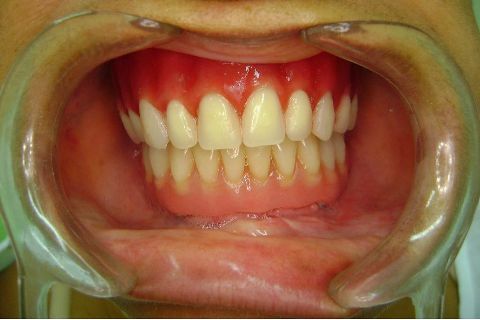

FASE PROTÉTICA DA REABILITAÇÃO EM MAXILA ATRÓFICA...incluindo a reabertura, instalação dos minipilares e PTR provisória reembasada sobre os cilindros de proteção.